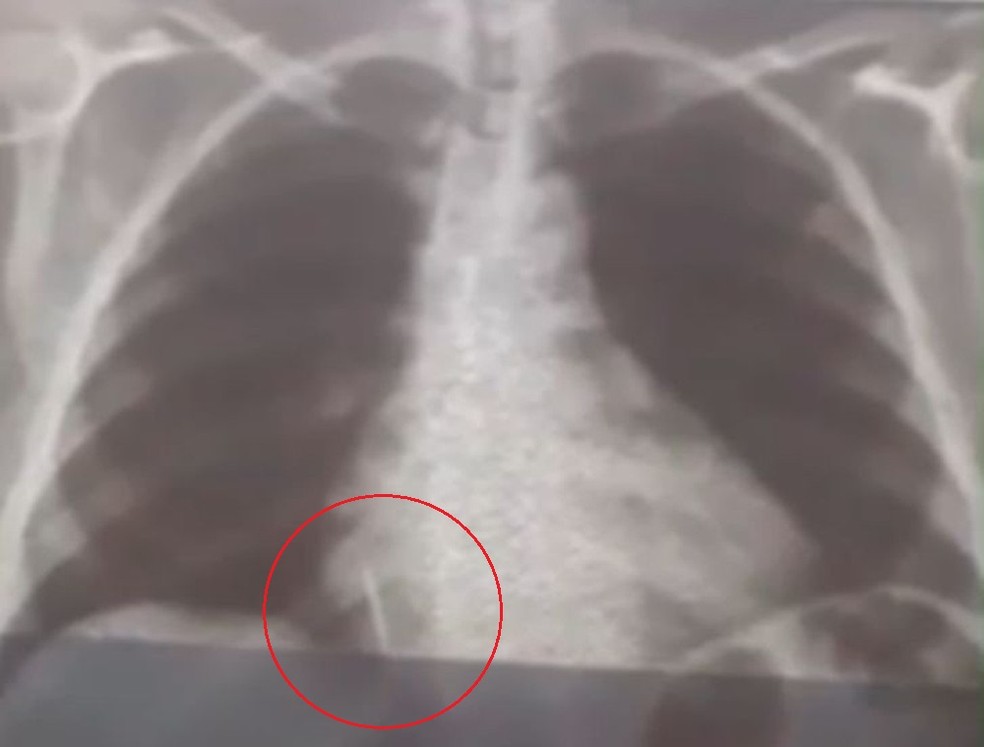

Uma paciente de 55 anos engoliu uma broca durante a extração de um dente em uma unidade de saúde no município de Lajes, Região Central potiguar (veja a imagem acima). O caso aconteceu no dia 26 de julho.

Iolanda Mariano de Melo Simplício está com o material alojado no pulmão deste então. O filho dela conta que a mãe sente muitas dores e já perdeu cerca de 10 quilos desde o ocorrido.

“A Secretaria Municipal de Saúde nos deu assistência para a realização dos exames. A gente foi para Natal inúmeras vezes com ela para fazer tomografia, raio-x, hemograma, risco cirúrgico, mas até agora nada. Já são quase 29 dias e praticamente não temos resposta. A gente quer uma solução, porque é um corpo estranho que está dentro do pulmão dela”, conta Rohnhalyson Mariano.